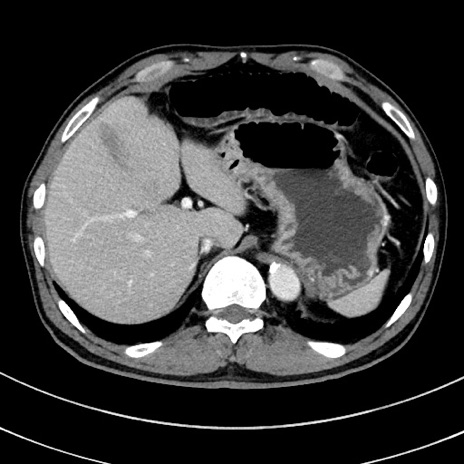

症例8(横断像)

【症例】 60歳代男性

【主訴】 黒色吐物

【現病歴】 4日前から嘔気自覚、2日前の朝食後にも嘔気あり、自分で手で嘔吐反射起こし嘔吐したところ血が混ざっていたため受診。

【既往歴】 5年前汎発性腹膜炎を伴う急性虫垂炎で手術、高血圧、前立腺肥大症、高脂血症

【身体所見】 腹部正中に手術癩痕あり 腹部平坦・軟圧痛なし膨満感あり

【データ】WBC 8400、CRP 4.54